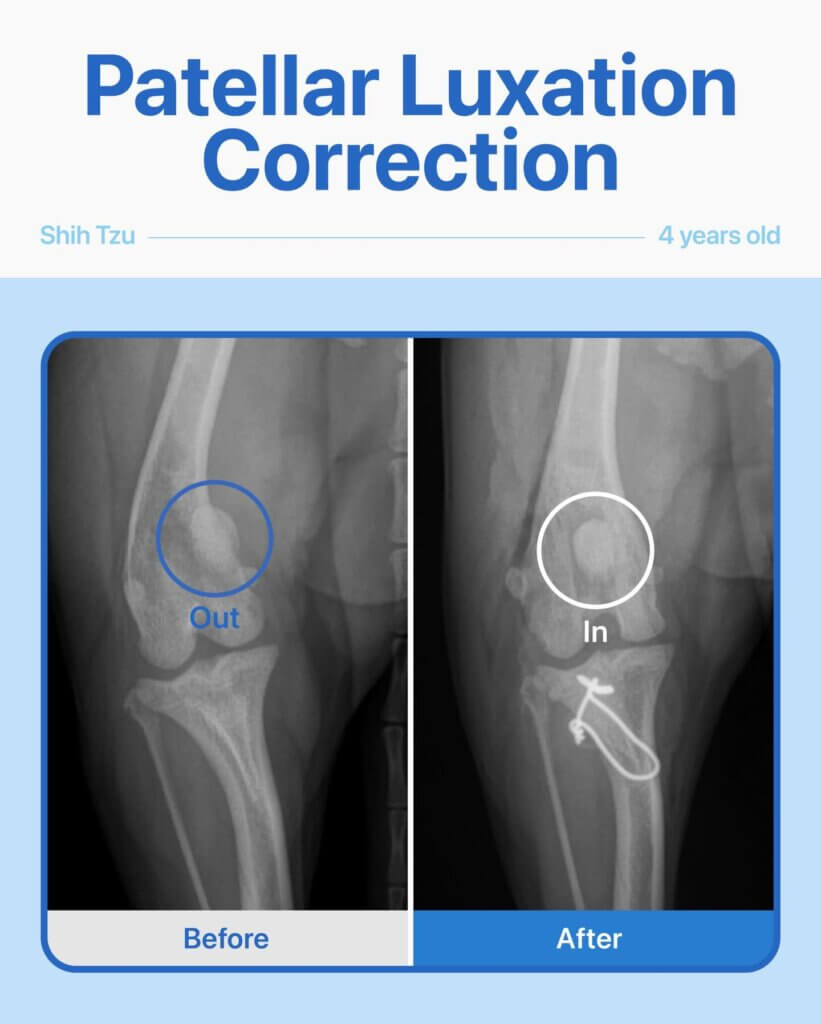

This sweet Shih Tzu came to us limping on her right hind leg, showing clear signs of discomfort and pain. After a thorough physical exam and radiographs, we discovered her kneecap (patellar) had slipped out of its normal position — a condition known as patellar luxation. Our team performed a patellar luxation repair surgery, and everything went smoothly. Throughout her recovery, she did wonderfully, and now she’s back to being her playful, happy self, moving comfortably and without pain again. Moments like this are why we love what we do.